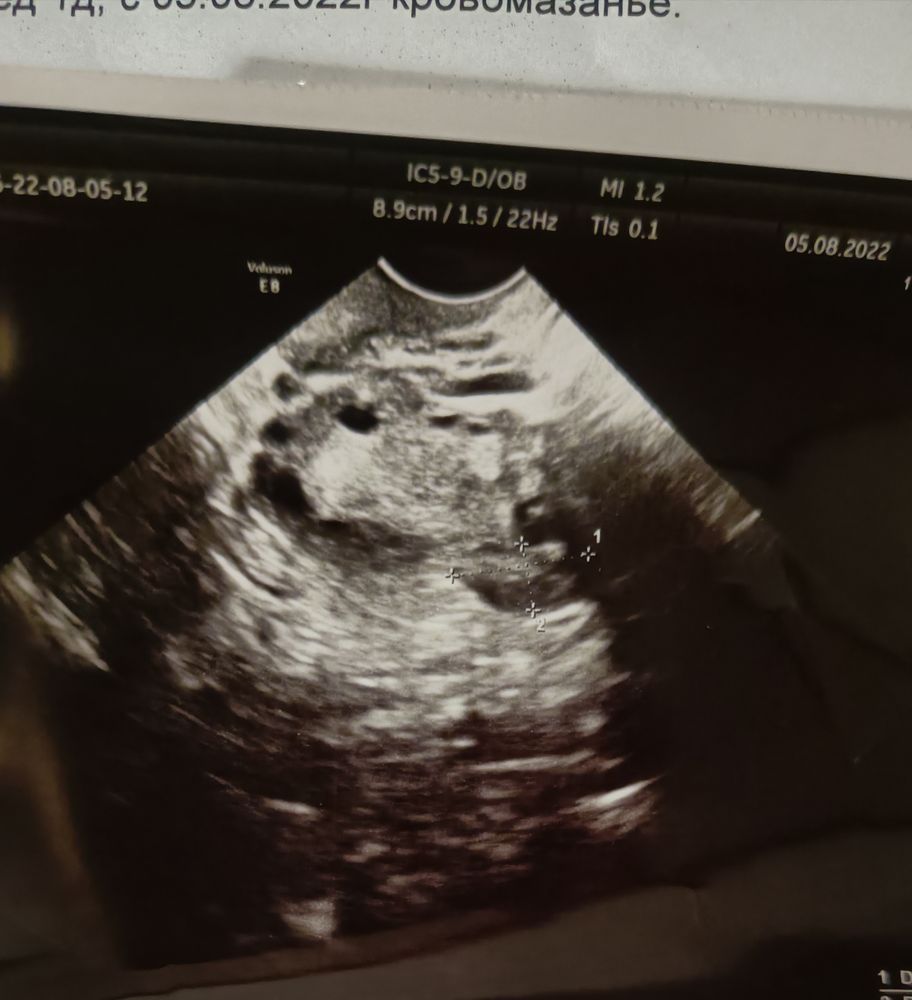

Девочки, вот результаты узи сегодня, хгч упал с 245 до 164 за 48 часов, узи уже после результатов хгч было, подозрение на ВБ, но при этом обнаружено солидное образование аж 19 мм, это при том что на моем сроке при нормальном то ХГЧ было бы яйцо максимум 5 мм, я что то сомневаюсь что это оно, плюс жидкости в Дугласе нет, я все таки склоняюсь к бхб, врач пока молчит, а я дюф не пью уже, и еще смутило что ЖТ хорошее и активное, странно если хгч так падает, плюс не понятно откуда кровило, как утром вышло чуть тёмной крови так тишина, даже мазни нет, и что за полость в дне матки, в общем одни непонятки...

angelova , вчера поясницу чуть тянуло вечером, а так вообще ничего нигде не болит, но у меня поясница и без беременности часто ноет, я вообще не уверена когда она на неё реагирует а когда сама по себе) вот фото